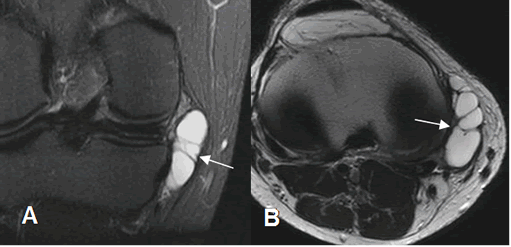

Fig 182. Bursitis anserina.

A: RM coronal en STIR y B: RM axial en T2. Lesión quística septada, en relación con los tendones de la pata de ganso, que corresponde a bursitis.